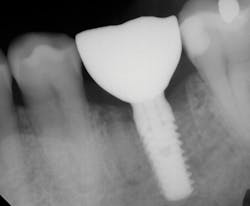

Being a network of small- to medium-sized private practice groups, we negotiated volume pricing on our favorite suite of manufacturer-direct systems. It is these systems that were uncovered during this process that we will highlight in the clinical portions of this series. We secured high-volume, manufacturer-direct, DSO-like pricing, and we call ourselves the Implant Alliance.In our practice of four dentists in Allen, Texas, we have been very intentional about making sure we can deliver incredibly high-quality dentistry at affordable rates for our patients. The case shown this month (figures 7–12; courtesy of Mike Dostal, DDS, FICOI) represents a very typical “I just need my tooth replaced” kind of day in our office. You see a patient in hygiene who has been missing a tooth for years and just didn’t want a bridge. Now, we can offer a simple appointment to place a flapless, sutureless implant, and the patient probably can go right back to work the same day.

The implant systems that satisfy this challenge the best for us are the iHex 1, 2, and 3 and MorsTorq systems by iH Biomedical. The iHex series is an internal hex that is compatible with most of the major internal hex systems. It incorporates platform switching, which allows for crestal or subcrestal placement. The designers created a multicompatibility surgical kit that minimizes the number of drills (often just one needed) used to place and restore the implants. The platforms are the same across most sizes, which reduces the number of abutments that must be stocked. Also, the implant, abutment, and cover screw are all included. These design features place this system at the top of the list when it comes to economics and excellence rolled into one package.